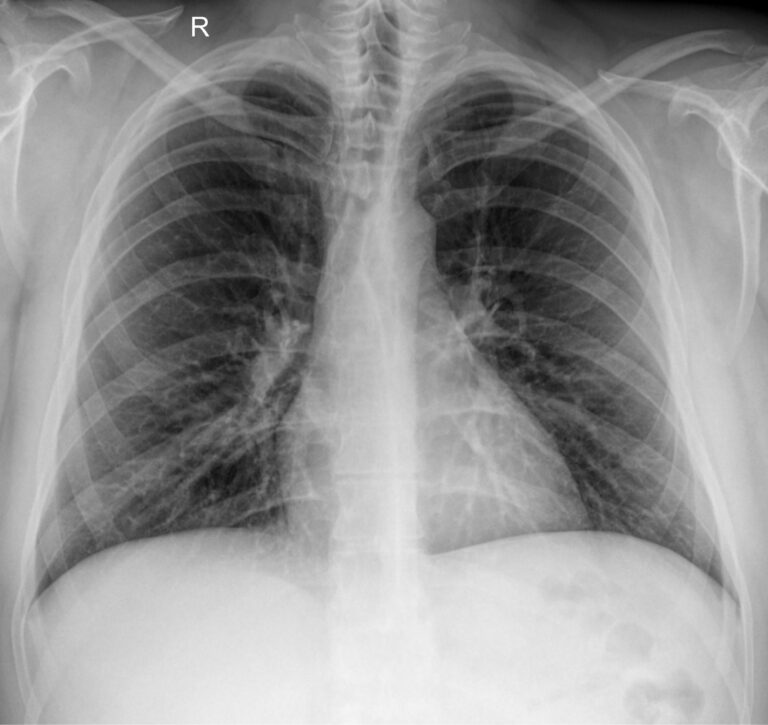

Диагностика с помощью рентгеновского излучения основана на его способности проходить сквозь живые и неживые объекты. В том числе, через тело человека. Органы разной плотности поглощают разное количество излучения, в результате на классическом негативном снимке наиболее плотные образования, кости, отображаются самыми светлыми, а наполненные воздухом ― почти черными. Мягкие ткани визуализируются как пятна серых оттенков. Участки, цвет и форма которых не типичны, говорят о патологии.

Снимок грудной клетки используют, чтобы получить изображение расположенных здесь органов: легких и дыхательных путей, контуров сердца с сосудами, а также позвоночника и костей. Обычно для диагноза достаточно одного снимка ― в прямой проекции, когда лучи идут сзади наперед. Иногда врач назначает снимок в боковой проекции, то есть слева или справа. Это необходимо, если требуется более точно определить сегмент поражения или достоверно исключить патологический процесс. Крайне редко требуются косые проекции, но они тоже бывают.

Что показывает рентген грудной клетки

На рентгенограмме видны следующие образования, расположенные в грудной клетке:

• Мягкие ткани: грудные мышцы, кожные складки;

• Костный скелет: ребра, ключицы, грудина, нечетко ― позвонки, в пожилом возрасте ― хрящи;

• Легочные поля: определяются их прозрачность, симметричность, легочный рисунок;

• Корни легких: топография, форма, структура, ширина;

• Средостение: положение сердца и сосудов, формирующих его дуги;

• Купол диафрагмы: четкость, местонахождение;

• Синусы: свободные или заполненные.